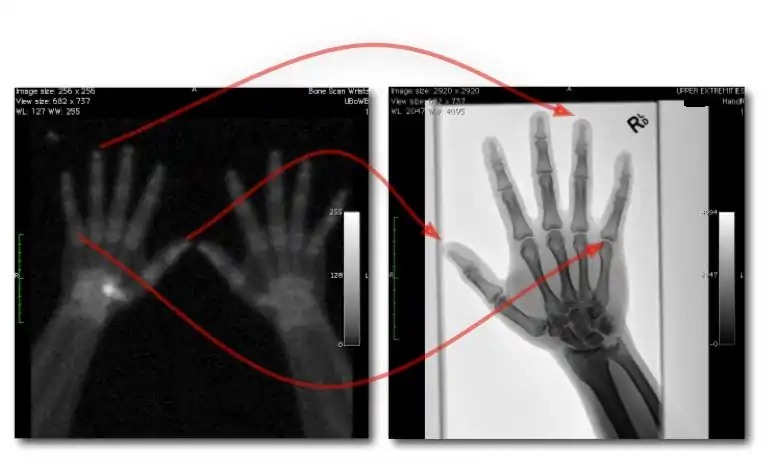

Dual-Energy Imaging

- CR and DR image receptors can generally be used for dual-energy radiography in either of two configurations:

- Dual exposures: where two separate exposures are used in applications where patient movement isn't an issue; and